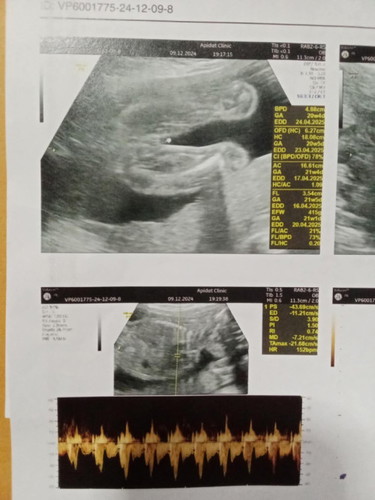

เเบบนี้ผู้หญิงไหมค่ะ

หมอบอกได้ลูกสาวเเต่เเม่ไม่เเน่ใจค่ะ

ลูกสาวคะเเม่ หวางขาไม่มีอะไรโผล่ ยินดีด้วยนะคะ🥰